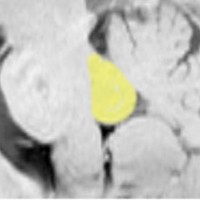

右側頭葉先端の腫瘍です。発症時にはMRIで異常所見がありませんでしたが,徐々に顕在化しました。ガドリニウム増強はなく一部のう胞性です。

4歳時に意識現存を伴う発作が1日3回くらいあるという難治性部分てんかんで発症しました。手術中の頭蓋内脳波で,下側頭回に激しい棘波と棘律動を認め,扁桃体への刺入電極でも棘波がありました。周辺脳にも棘波はありましたが,病変(腫瘍)と扁桃体を切除するのみの手術を行いました (lesionectomy and amygdalectomy)。手術後13年が経過しますが発作はありません。病理では,腫瘍組織内に神経節細胞はなく,皮質異形成 cortical dysplasiaあるいはグリオーマ様病変 gliomatous lesionという診断でした。1p/19qに欠失はありませんでしたが,乏突起膠腫も否定できない周囲灰白質に浸潤性の腫瘍でした。この例はlow-grade gliomaでしょうが確定病理診断はできないものです。どちらであっても,基本的にグレード1ですから,手術後再発はしません。